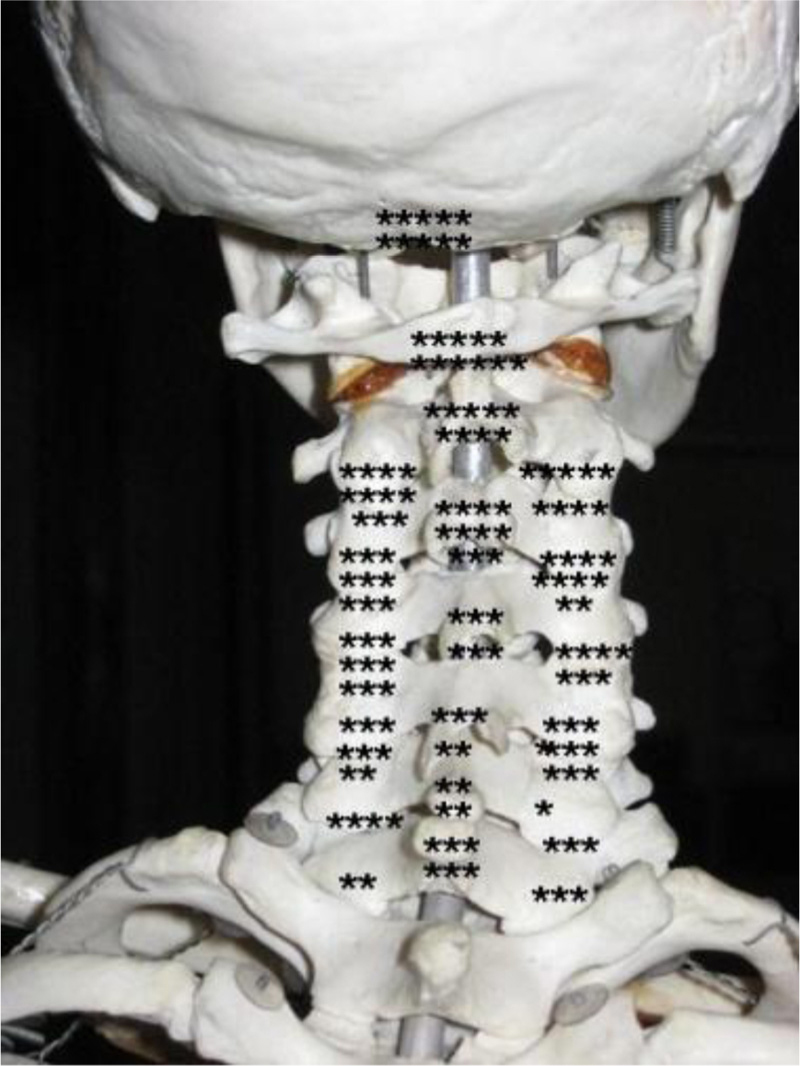

Distribution of high blood flow in 20 patients. Each dot represents the localization of high blood flow found in a region in a single patient (regardless of intensity).